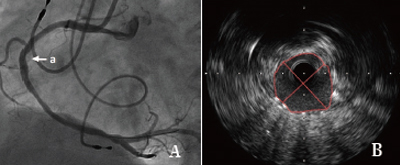

该患者于凌晨5点睡觉时突发胸痛,疼痛感向左侧肩部及后背放射,伴全身出汗以及恶心,并呕吐一次,胸口疼痛持续不缓解,由家里人送入我院急诊科,急诊科医师立即行心电图,结果提示心脏前壁、下壁、后壁心肌梗死,随后检验科回报心脏损伤标记物显著升高,急性广泛心肌梗死诊断明确,在张萍主任,缪国斌主任医师,薛亚军主治医师评估患者病情后,立即行冠状动脉造影显示冠状动脉左主干、前降支、左回旋支以及右回旋支均有广泛狭窄,情况复杂,随后在王伟民教授指导下使用血管内超声技术评估患者病变血管严重程度,并精确定位病变范围,支架大小,同时应用血管内超声技术评价支架植入后贴壁状况等,体现了我院倡导的“三精”医疗理念。术后患者平安返回病房,现病情恢复良好,胸痛症状未在发作。

血管内超声(intravenous ultrasound,IVUS) 是无创性的超声技术和有创性的导管技术相结合的一种新的诊断方法。运用该方法与传统的冠脉造影技术相结合可以准确评估血管的管壁形态及血管狭窄程度,在冠心病的介入性诊疗中有很高的指导价值。

传统冠脉造影只能显示管腔的情况,不能显示病变所在的管壁和粥样斑块,不能提供粥样斑块形态和性质的详细情况,有可能使医生低估冠脉狭窄的程度。这就使得依据冠脉造影评价冠脉粥样硬化和介入治疗疗效的准确度降低。血管内超声是利用导管将一高频微型超声探头导入血管腔内进行探测,再经电子成像系统来显示心血管组织结构和几何形态的微细解剖信息。由于超声探头直接置于血管腔内探测,因此,血管内超声不仅可准确测量管腔及粥样斑块或纤维斑块的大小,更重要的是它可提供粥样斑块的大体组织信息,在显示因介入治疗所致的复杂的病变形态时明显优于造影。